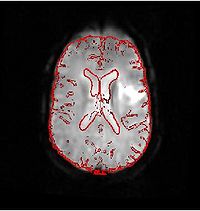

ConnectivityMap.png

Stochastic Tractography

This work calculates posterior distributions of white matter fiber tract parameters given diffusion observations in a DWI volume. More...